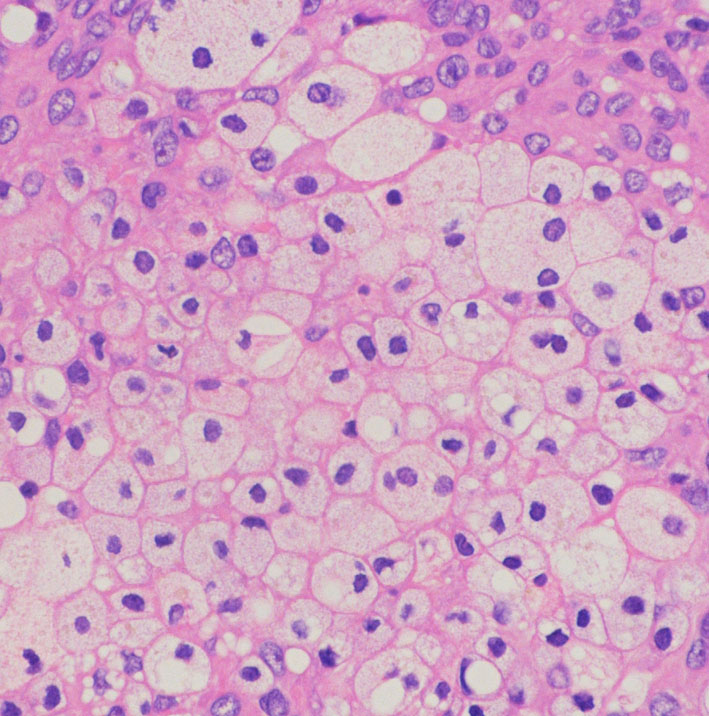

microcystic meningioma 微小のう胞性髄膜腫

多くののう胞を含む髄膜腫です。実質部分では類円形の腫大核を有し核小体が明瞭な細胞がシート状に増生しています。細胞密度が高い部分がありますが,MIB-1染色率は2%程度です。WHO grade 1 microcystic meningiomaの像です。